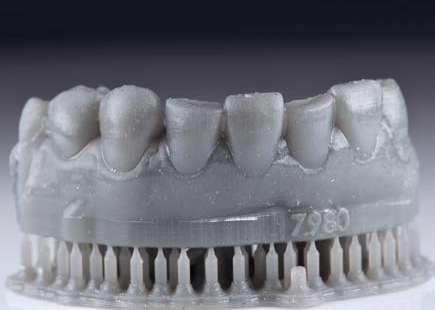

CARILLAS DIGITALMENTE GUIADAS. SELECCIÓN DE UN CASO

Aunque la mayoría de las personas tienen la creencia errónea de que las carillas estéticas son un tratamiento novedoso y actual, en realidad éstas fueron inventadas por el Dr. Charles Pincus en los años 20, coincidiendo el auge de la odontología en Estados Unidos con el paso del cine mudo al sonoro. A partir de ese momento las carillas han ido evolucionando, sobre todo en cuanto a materiales y adhesión. Actualmente damos un salto más en esta evolución y añadimos la tecnología para convertir este tratamiento tan conocido en uno mucho más predecible y estable en el tiempo.

Introducción

Los procesos y protocolos en la odontología han pasado por grandes cambios en los últimos tiempos. Bien sea en el laboratorio o en la clínica dental, la principal preocupación es conseguir flujos de trabajo más predecibles pero que a la vez sean sencillos para poder ser reproducidos por la gran mayoría de los profesionales; haciendo que procedimientos complejos puedan apoyarse en la tecnología para ganar sencillez y calidad en la finalización.

Seguir una propuesta previa de tratamiento desde un mockup y garantizar que la finalización sea tal cual lo prometido, depende de muchos factores; desde el material que seleccionamos, la técnica de finalización y también la buena y correcta preparación por parte del clínico.

En cuanto a eso, sabemos también que el éxito de las restauraciones entre otras cosas está muy vinculado a la cantidad de preparación (2, 3, 4), procedimiento que no es fácil controlar si no hacemos uso de la tecnología.

Diferentes técnicas de preparación y control de espesores siempre se han discutido, desde el uso de guías de silicona hasta el uso de fresas calibradas sobre el mockup (5, 6).

Actualmente es posible planificar de manera digital y analizar previamente al acto de preparación, toda la cantidad de diente que debe ser removida para conseguir llegar al resultado prometido. El uso de guías de preparación con turbinas especialmente desarrolladas para ello hará posible que lo que se ha planificado en la pantalla, se lleve a cabo en la clínica de una forma fiel.

De esta manera, los resultados estéticos se harán personalizados, decidiendo para cada caso lo mejor en función de cada situación y sus características biológicas, respetando al máximo los tejidos, ventaja que con las técnicas convencionales no era posible realizar.

Por ese motivo, en este artículo, presentamos un caso que reúne estas dificultades añadidas pero que aún así se beneficia del uso de esta tecnología para su ejecución.

Presentación del caso clínico

A continuación, presentamos el caso clínico de una paciente con unos dientes mal posicionados y con una coloración acentuada sobre todo a nivel de los centrales que además presentaban extensas restauraciones antiguas de composite en interproximal cerrando diastemas que originalmente presentaba la paciente. Estos dientes necesitarán tener una preparación un poco más subgingival y también removido previamente todo el composite antiguo con el objetivo de camuflar este cambio de color y evitar zonas visiblemente no estéticas.

Además, lo combinaremos con unas carillas inyectadas inferiores también planificadas digitalmente y sin tallado, para crear una armonía y equilibrio con la parte superior.

En estos casos donde tenemos que camuflar sustratos oscuros o los dientes tienen una malposición severa haremos una preparación previa de los márgenes y zonas especialmente retentivas para mejorar la inserción de nuestras carillas. Por tanto, podemos beneficiarnos de las ventajas de la planificación digital, en cualquier caso, siendo necesario en los casos más complejos una preparación previa.

1 Inicio.

Como podemos observar la paciente tenía un sustrato muy desfavorable, con un color aproximado de A3,5 Vita.

Para la arcada inferior se optó por unas carillas inyectadas, completamente respetuosas con los tejidos, que nos permiten mejorar la apariencia de los dientes y dar así una mayor armonía con la parte superior. Al ser también planificadas digitalmente aseguramos que lo que colocamos en boca sea una fiel reproducción del diseño previamente aceptado por el paciente y el profesional.

Mockup.

En la arcada superior por el contrario se decidió poner unas carillas de disilicato para poder cubrir las expectativas de la paciente y ajustar el color al que ella deseaba, bajando casi en 5 tonos el color final. Se planificaron preparaciones digitales conservadoras.

La tecnología digital permite lograr el equilibrio de espesores ideal para cada caso, así como un eje de inserción adecuado. Todo esto permite dar una garantía de longevidad a las restauraciones planificadas.

En este caso se realizó una preparación previa a la preparación guiada en los márgenes y zonas interproximales, para camuflar el sustrato y dar una correcta inserción; y posteriormente se utilizaron unas guías de tallado diseñadas digitalmente para obtener los resultados precisos y predecibles que requería el caso.

La preparación previa junto a la preparación guiada, resultaron en un equilibrio ideal para los espesores mínimos que requería el caso. Se realizó una prueba en seco para valorar el ajuste final de las restauraciones.

Para cementar las carillas y evitar movimientos no controlados y una incorrecta cementación, utilizaremos una guía de posicionamiento simultáneo, esta guía no es de cementación en bloque ya que las carillas están perfectamente individualizadas. Únicamente sirven para llevar a la boca del paciente las carillas y cementarlas de una forma 100% segura, evitando el estrés que genera un posible movimiento durante la cementación y acelerando los tiempos de trabajo.

Consiguiendo así una perfecta adaptación de los márgenes de las restauraciones y la sensación de naturalidad e integración que se observa en la imagen final.

Como se puede observar en la imagen comparativa, la planificación se reproduce de una forma fiel a lo que se había planificado y aceptado por la paciente. Por tanto, no es una técnica susceptible al operador, que se realiza controlando mucho mejor los tiempos y los resultados obtenidos.